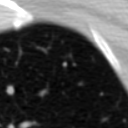

The current study focuses on lung nodule retrieval from a database of CT scans, where patches taken from CT slices of pulmonary nodules are to be mapped into an embedding. LIDC-IDRI [5] is a dataset of thoracic CT scans of 1,010 patients. All the scans were annotated by up to four radiologists, where each one identified, segmented and evaluated separately the lung nodules of a diameter above . Their evaluation also included ratings for a set of 9 characteristics: Subtlety, Internal structure, Calcification, Sphericity, Margin, Lobulation, Spiculation, Texture and Malignancy. The rating system was based on a discrete score of 1-5. Four examples of nodule patches are illustrated in Figure 2: 2 benign (a, b) and 2 malignant (c, d). A rounded vector of the mean rating is bellow each nodule, with the characteristics ordered according to the listing above. The most prominent difference between a and b is the calcification: 3 (solid) and 6 (absent) accordingly. d compared to c has a more defined margin, is more lobulated, but less spiculated. The malignancy score is used to define malignancy classes: score of 1-2 is benign, score of 3 is unknown, and a score of 4-5 is malignant.

(a) Benign

3, 1, 3, 3, 4, 3, 1, 5, 1

(b) Benign

3, 1, 6, 5, 5, 1, 1, 5, 2

(c) Malignant

5, 1, 6, 3, 3, 4, 1, 5, 5

(d) Malignant

4, 1, 6, 3, 4, 2, 2, 5, 4